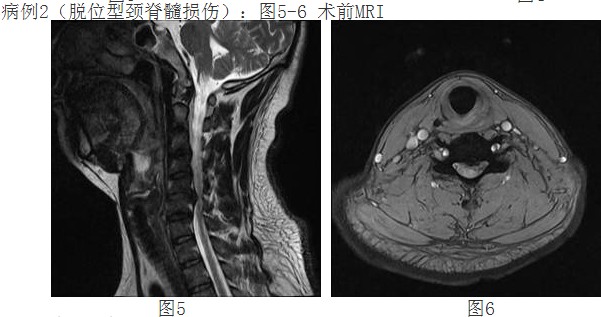

来自惠州农村李阿婆有多年的颈椎病病史,一月前颈部症状加重出现颈痛及四肢麻木、刺痛,不能耐受,上肢手臂力量及握力下降。经人介绍前来我院,经惠州三院脊柱外科谭志宏主任仔细检查,并结合颈椎MRI,明确诊断为颈4/5、颈5/6椎间盘突出症并椎管狭窄,属脊髓型颈椎病。同时认为如果采取保守治疗问题根本解决不了,只有手术治疗才有康复的希望。颈椎手术在脊柱方面属高难度、高风险手术,在外科手术分级中属于最高级别的Ⅳ级手术。

经过谭主任和全科医护人员充分的术前准备和讨论,对患者实施了颈椎前路颈4/5、颈5/6椎间盘摘除、颈5椎体次全切除、椎管减压钛网植骨融合、颈前路钛板固定术。手术取得了成功。术后第二天,李阿婆的四肢麻木就明显减轻,握手能力和手臂力量都明显好转。